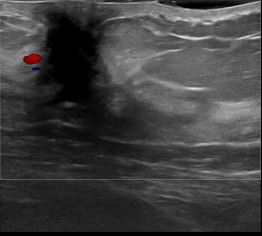

상기환자는 외부검사 이상소견으로 내원하신 40대후반 여성분으로 의심스러운 좌측혹 조직검사 시행해 제자리암으로 진단되었습니다